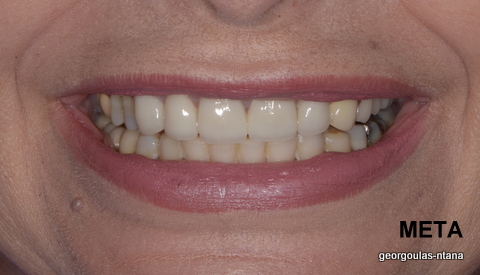

ΠΡΟΣΘΕΤΙΚΗ ΑΠΟΚΑΤΑΣΤΑΣΗ ΣΤΗΝ ΑΝΩ Κ ΚΑΤΩ ΓΝΑΘΟ ΚΑΙ ΤΟΠΟΘΕΤΗΣΗ ΕΜΦΥΤΕΥΜΑΤΩΝ ΜΕ ΚΛΕΙΣΤΗ ΑΝΥΨΩΣΗ ΙΓΜΟΡΕΙΟΥ

περισσότερα...